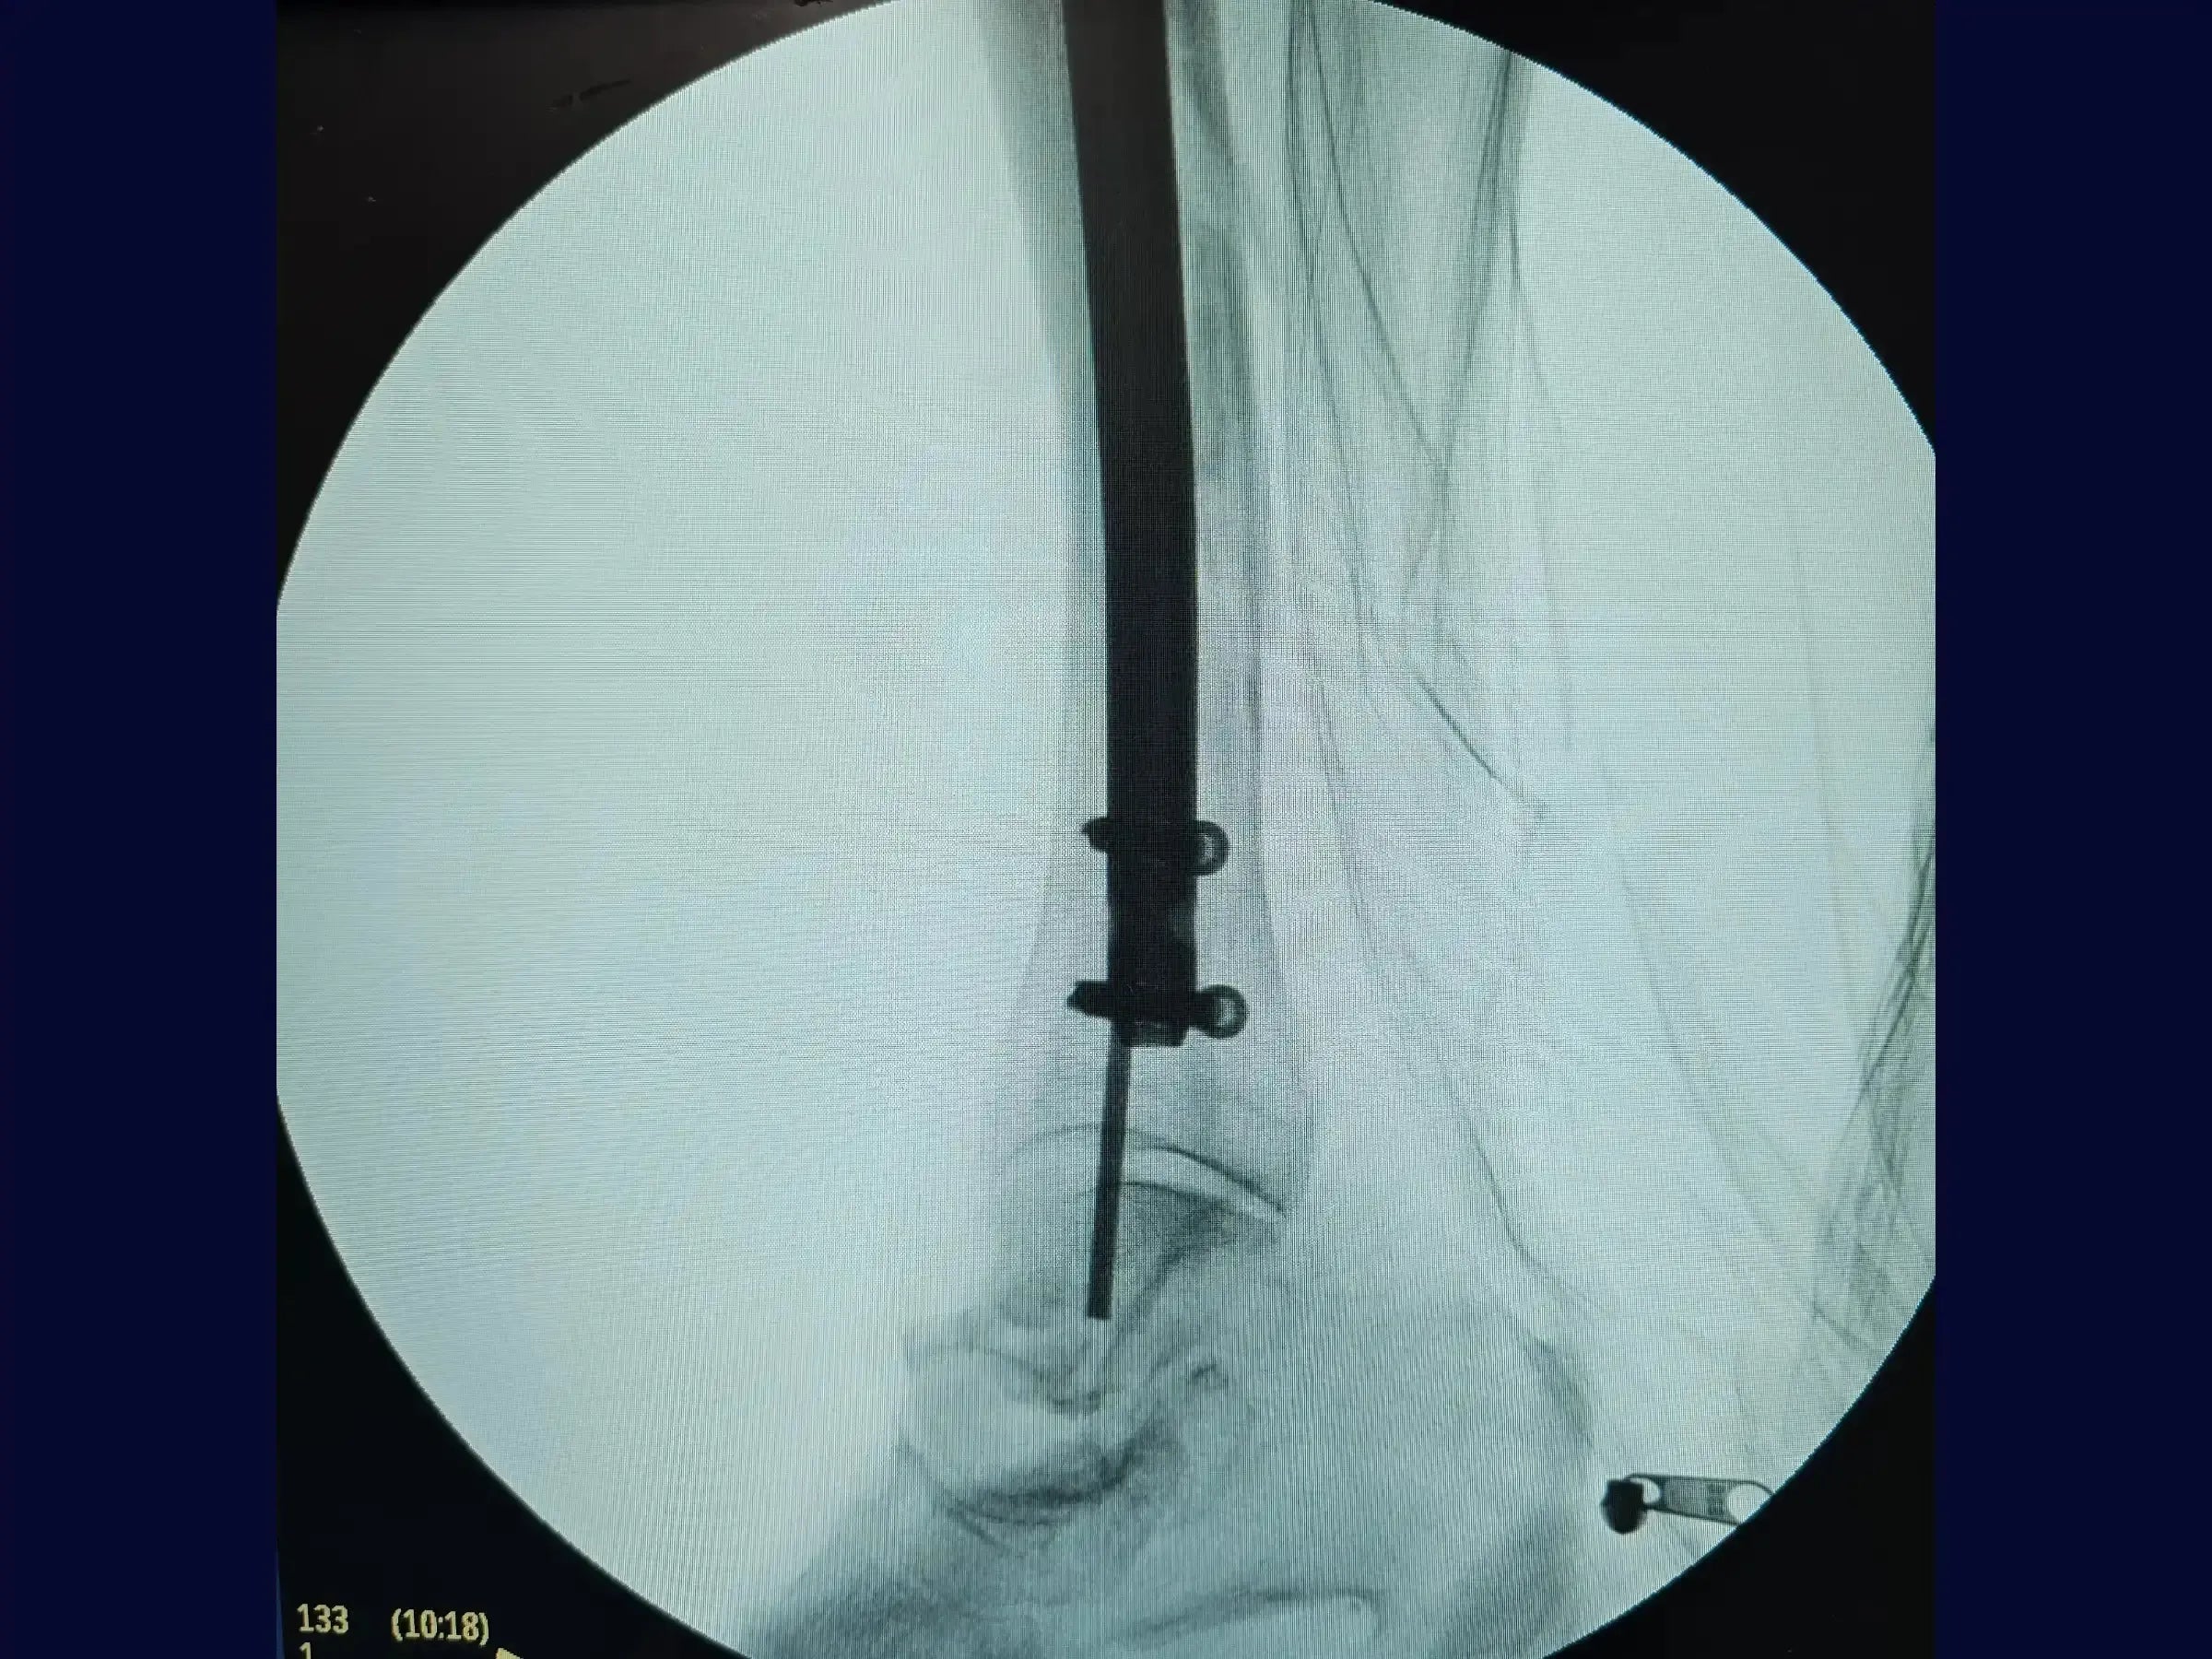

- Redução e Inserção do Fio Guia: Metodologia para redução percutânea com pinça, com progressão do fio guia olivado e verificação de sua centralização nas incidências AP e perfil, visando o centro do tornozelo.

- Fresagem e Introdução da Haste Intramedular: Técnicas de fresagem para alargar o canal medular e introdução da haste de maior diâmetro, mantendo a camisa de proteção e protegendo a cartilagem articular.

- Bloqueio Proximal e Distal: Execução do bloqueio proximal percutaneamente com o paciente mantendo a perna em posição estável, e técnica de "mão livre" para os parafusos de bloqueio distal, com marcação precisa da pele para evitar atrito com partes moles.